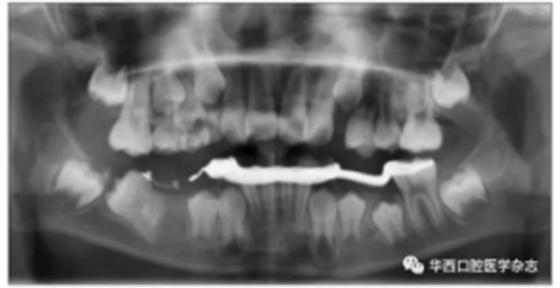

46牙開窗并將舌側(cè)扣粘接于近中面。用玻璃離子將鑄造板粘接在下頜,橡皮鏈通過83牙遠中的牽引鉤和46牙上的舌側(cè)扣相連,橡皮鏈牽引時對46牙產(chǎn)生一個順時針旋轉(zhuǎn)的作用力。術(shù)中牽引1個月時,見46牙產(chǎn)生順時針旋轉(zhuǎn)(圖5、6)。治療5個月時,46牙產(chǎn)生明顯的順時針旋轉(zhuǎn),基本直立(圖7),由于此時下頜雙側(cè)乳尖牙脫落,下頜鑄造板無法固位,于是拆除矯治器,觀察隨診,待后期其余牙齒萌出后行全口固定正畸矯治。

圖 6 治療1個月全景片

圖 7 治療5個月全景片